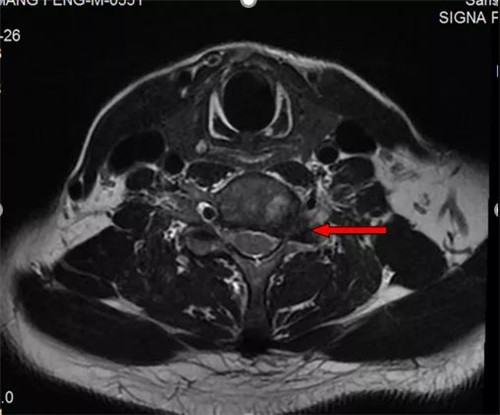

磁共振显示C6-7椎间盘左外侧突出,压迫颈神经根

“C6-7椎间盘左外侧突出,压迫了颈部神经根,必须切除突出部分。不过不用担心,可以做微创手术,从脖子后面开一个很小的创口,利用颈椎椎间孔镜将髓核摘除,再进行神经根粘连松解即可。”脊柱关节外科主任潘磊博士拿着脊椎的模型向陈大爷解释道。